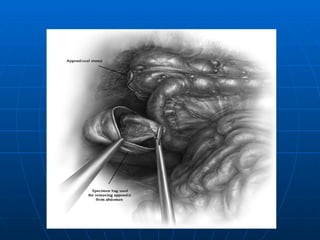

INCISIONES T MB PMD MIU

TRATAMIENTO CONVENCIONAL APENDICECTOMIA: 1.- Localización del apéndice 2.- Transección del meso (arteria) 3.- Sección de la base (coprostasia) 4.- Manejo del Muñon( ligadura simple, inversión o combinación de ambos,pto. En Z o jareta) APENDICECTOMIA RETROGRADA PLASTRON APENDICULAR (Muñon libre + Drenaje) PERITONITIS DIFUSA (Lavado Peritoneal) APENDICE NORMAL

TRATAMIENTO CONVENCIONAL APENDICECTOMIA:1.- Localización del apéndice 2.- Transección del meso (arteria) 3.- Sección de la base (coprostasia) 4.- Manejo del Muñon( ligadura simple, inversión o combinación de ambos,pto. En Z o jareta) APENDICECTOMIA RETROGRADA PLASTRON APENDICULAR (Muñon libre + Drenaje) PERITONITIS DIFUSA (Lavado Peritoneal) APENDICE NORMAL